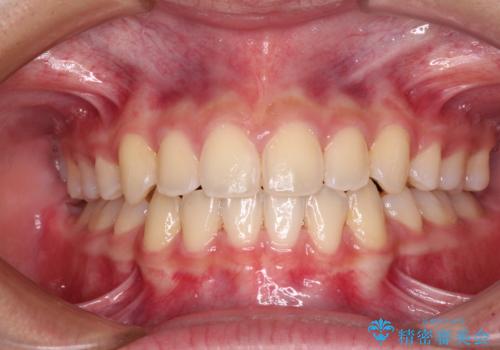

出っ歯を改善した後に真っ白な歯に 矯正歯科治療と審美歯科治療